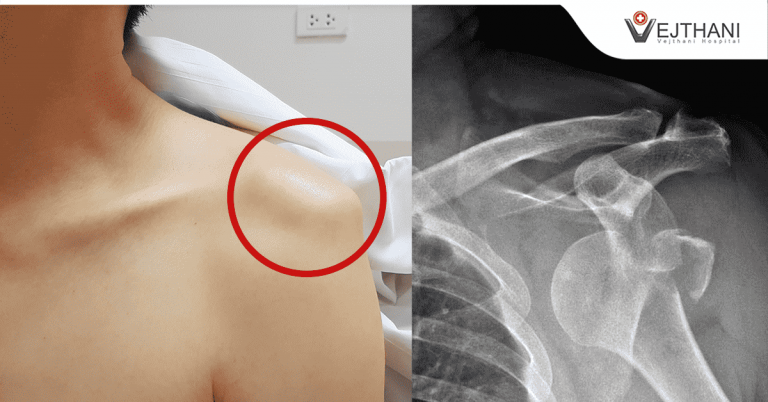

“Recurrent Shoulder Dislocation” is Treatable

Dislocated shoulder is a common disorder caused by a fall or bumping while playing high-impact sports, that causes the upper arm bone to pop out of the cup-shaped socket of the shoulder blade.